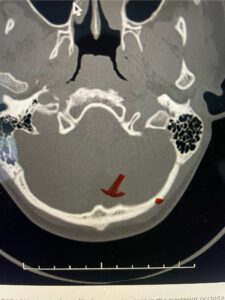

Fig. 2b: Axial CT scan of the brain demonstrating the thickness of the midline keel (red arrow) compared to the more lateral subocciput (red dot) making the keel ideal place for screw fixation

Fig. 6c: Axial cervical CT scan demonstrating a very thin right C2 isthmus (red arrow) compared to left side.